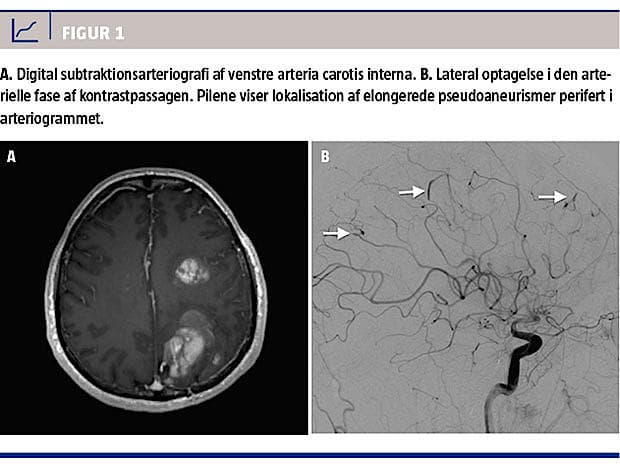

Et år senere fik patienten atter symptomer i form af pludseligt indsættende afasi og højresidig hemiparese. CT af cerebrum viste multiple parenkymatøse hæmatomer i venstre hemisfære. Gentagne MR-skanninger foretaget over de følgende måneder viste vækst af de hæmoragiske områder (Figur 1A). En ekkokardiografi viste ingen tegn til recidiv af myksom. En hjernebiopsi med histologisk undersøgelse viste ukarakteristiske forandringer uden tegn til infektion eller malignitet. Ved cerebral angiografi fandt man multiple fusiforme aneurismer på perifere a. cerebri media-grene bilateralt (Figur 1B).

Cerebral aneurysm following a cardiac myxoma is a rare neurological complication. We report a 50-year-old man who developed cerebral aneurysms one year after resection of a cardiac myxoma. Magnetic resonance imaging of the brain showed features of intracranial hemorrhage. Digital subtraction angiography showed several fusiform intracranial aneurysms bilaterally in the middle cerebral artery. Finally, we discuss potential molecular mechanisms of the development of myxomatous aneurysms.